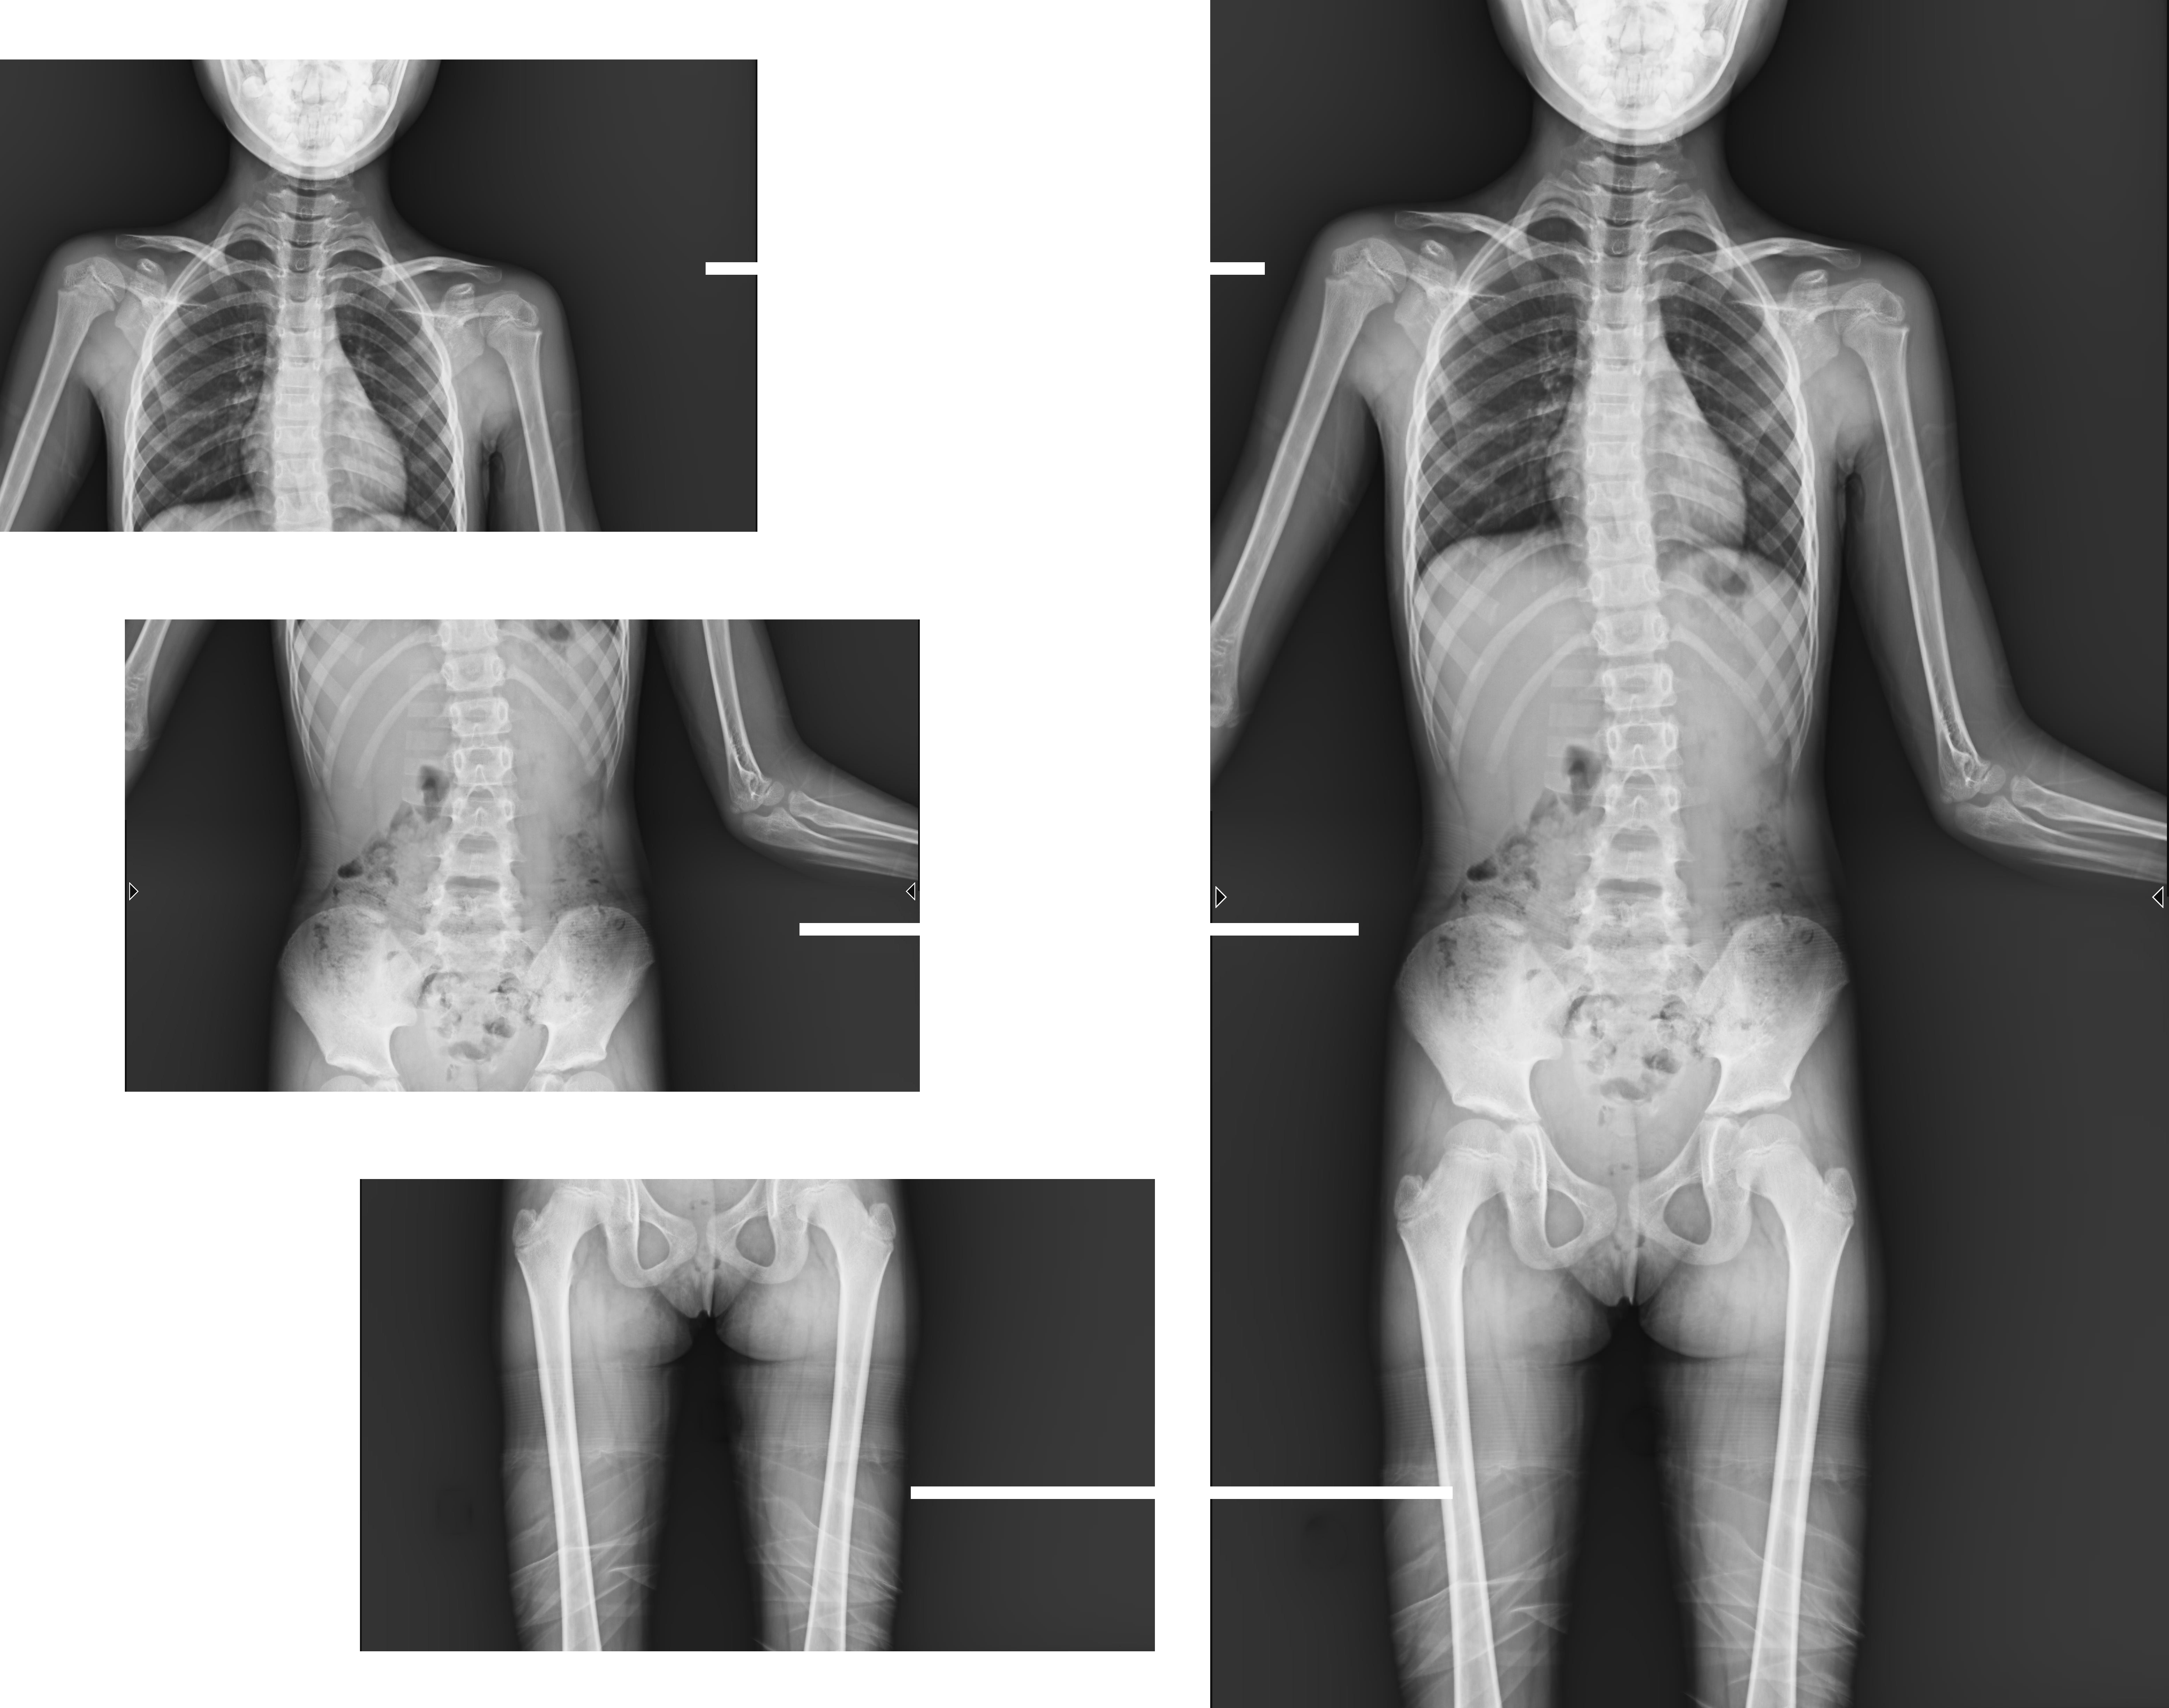

近年來,多發(fā)于青少年的脊柱側(cè)彎畸形,及骨性關(guān)節(jié)炎、風(fēng)濕性關(guān)節(jié)炎、雙下肢畸形(膝關(guān)節(jié)內(nèi)外翻、X型O型腿等)等骨科常見病發(fā)病率逐年增長(zhǎng),病癥常常累及下肢髖關(guān)節(jié)、膝關(guān)節(jié)、踝關(guān)節(jié)三個(gè)負(fù)重關(guān)節(jié),嚴(yán)重危害患者健康

動(dòng)態(tài)DRF以革新的動(dòng)態(tài)平板探測(cè)器作為全新的數(shù)碼載體,臨床應(yīng)用廣泛,在婦幼檢查中有著重要的臨床價(jià)值。